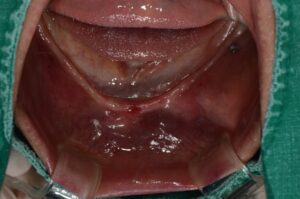

위 환자분은 하악에 전체 틀니를

사용하셨는데 틀니의 유지력이 부족하여

대부분 사용을 하지 않으신다고 하셨는데,

육안으로 보기에도 오랜 시간 틀니의 사용으로

잇몸뼈가 많이 소실 되어 있는 상태였어요.